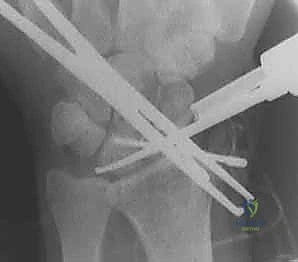

4. الرد التشريحي للعظام (Anatomic Reduction)

هذه هي الخطوة الأكثر حساسية. باستخدام أسلاك كيرشنر (K-wires) كـ "عصي تحكم" (Joysticks)، يقوم الدكتور هطيف بتصحيح تشوه DISI. يتم تدوير العظم الزورقي للخلف (تمديد) وتدوير العظم الهلالي للأمام (انثناء) حتى يتم استعادة الزاوية الطبيعية (46 درجة) وتختفي الفجوة بينهما تماماً.

5. الحفر وتمرير السلك الدليلي (Drilling & Guide Wire)

بمجرد التأكد من المحاذاة المثالية عبر جهاز الأشعة السينية اللحظي (C-arm Fluoroscopy) داخل غرفة العمليات، يتم إدخال سلك دليلي رفيع جداً يمر من العظم الزورقي مخترقاً إياه ليصل إلى العظم الهلالي في مسار دقيق للغاية.